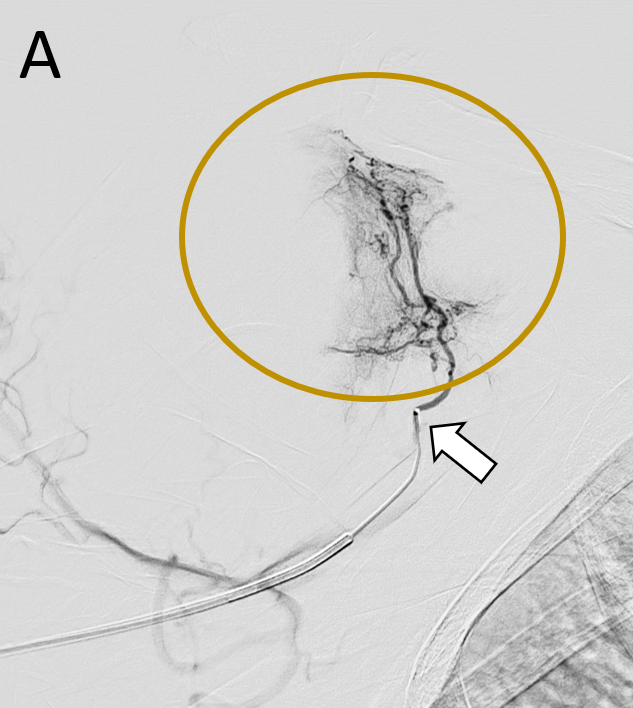

The procedure is typically performed on an outpatient basis, with a low complication rate and minimal recovery time. An arteriography of the upper or lower limb is performed depending on the joint to be treated. A 3F to 6F catheter is usually employed and the use of small microcatheters, from 1.7F to 1.9F, is recommended. The target of the embolization is the disappearance of the hypervascularized areas called “blush areas” (Figures 1 and 2), for which different types of materials, spheres, imipenem/cilastatin or lipiodol mixed with contrast can be used as embolic agents [10–12].

Figure 2. A. Super-selective angiography with the microcatheter from the coracoid artery (white arrow). Blush enhancement of the rotator interval (circle). B. The final angiography confirms the patency of the coracoid artery and the disappearance of the initial arterial blush.